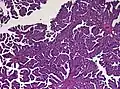

The tumor is neuroectodermal in origin and similar in structure to a normal choroid plexus. They may be created by epithelial cells of the choroid plexus. Papillary fronds lined by bland columnar epithelium are visible under the microscope. Normal absences include mitotic activity, nuclear pleomorphism, and necrosis.[10] Tumors have positive immunohistochemistry for cytokeratin, vimentin, podoplanin, and S-100.[11] Up to 20% of choroid plexus papilloma patients may test positive for glial fibrillary acidic protein (GFAP).[12] Studies have found that fourth ventricle cancers express more S100 than lateral ventricle tumors, and older patients (over 20 years) express more GFAP and transthyretin than younger patients.[13] Some individuals with choroid plexus papilloma have germline TP53 gene mutations, according to genetic analyses.[14] These cancers rarely exhibit nuclear p53 protein positivity. Aicardi syndrome, hypomelanosis of Ito, and 9p duplication are syndromic correlations of choroid plexus papilloma.

Plexuspapillom Overview